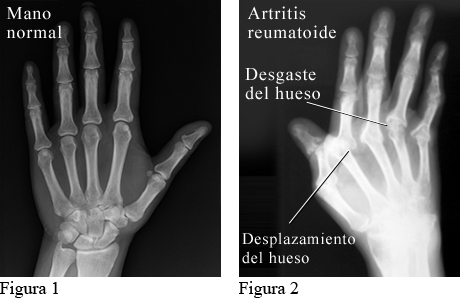

Radiografía de artritis reumatoide en las manos